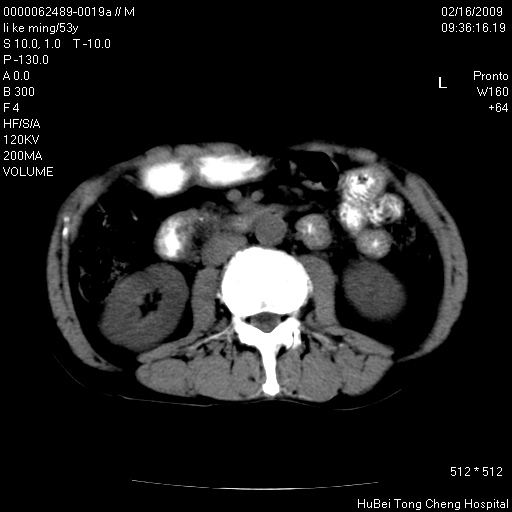

以下是引用卜一在2009-2-16 16:13:00的发言:[br]胰胆管扩张,末端明显狭窄 梗阻,胰头及十二指降段壶腹部结构紊乱。多考虑:十二指降段壶腹部癌!

以下是引用zsl6918在2009-2-17 8:48:00的发言:[br]符合胰头癌侵犯十二指肠。